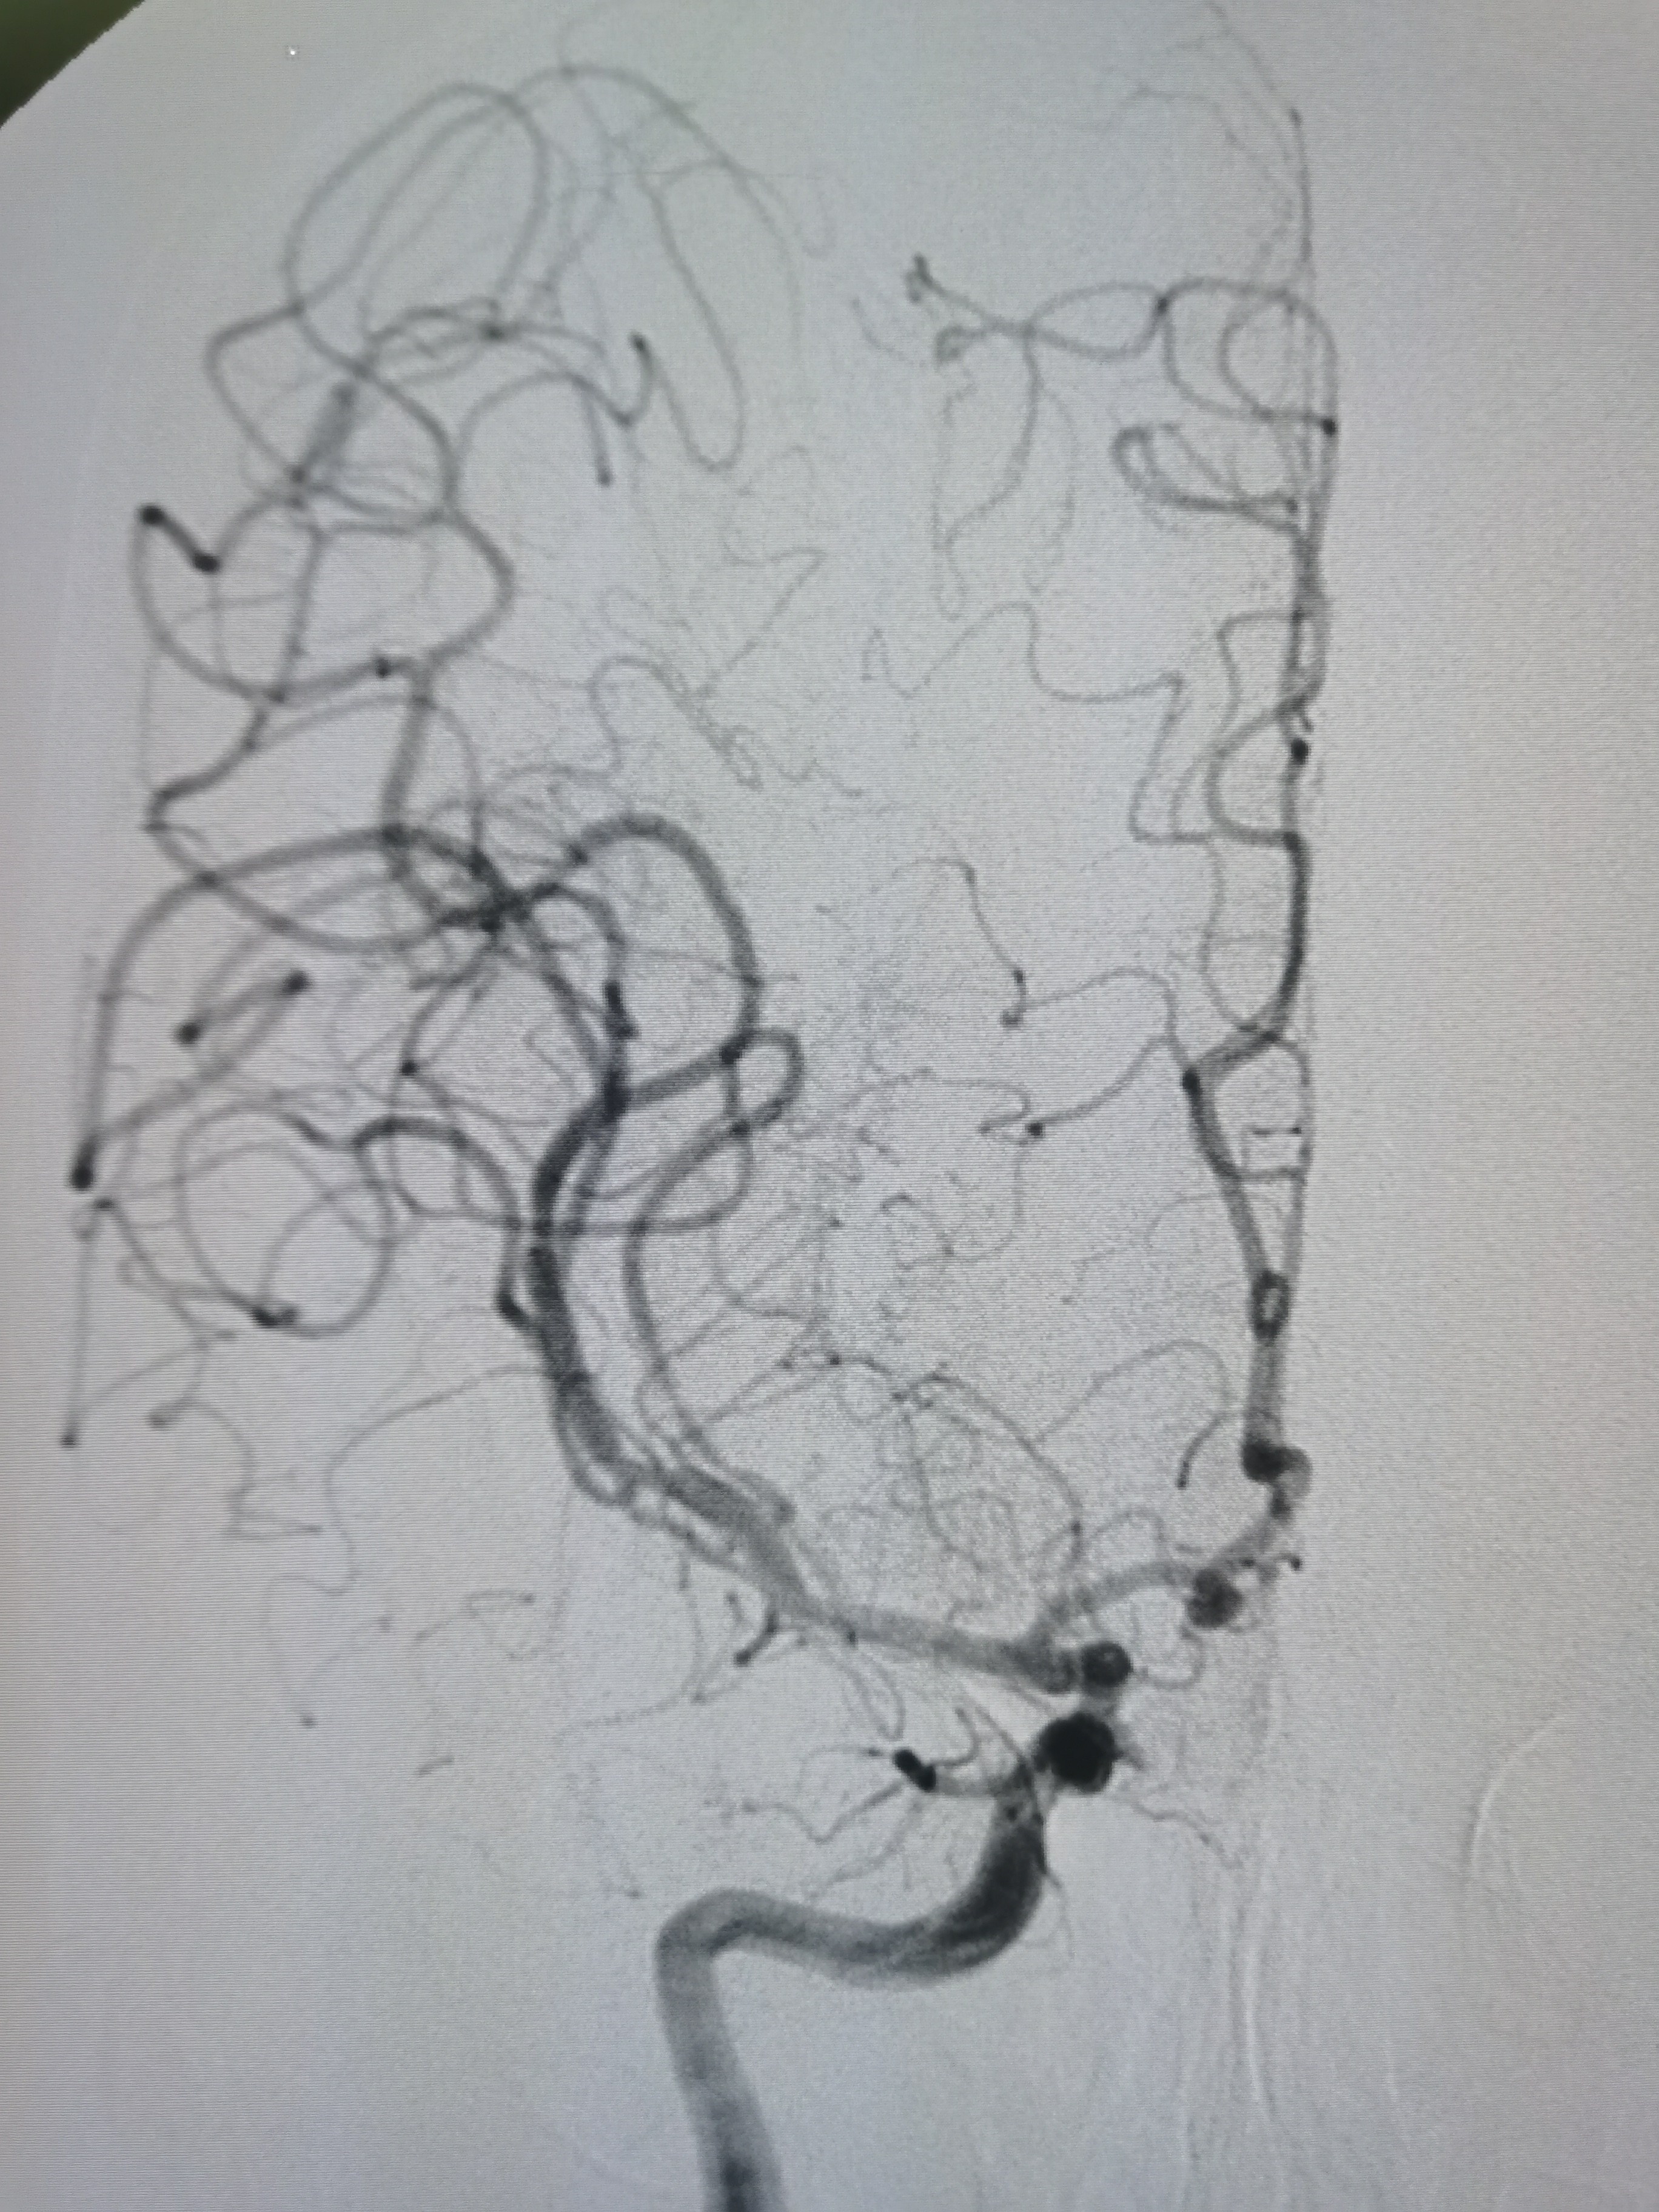

侧位见左侧大脑中动脉闭塞。

晚期可见左侧大脑中动脉返流。

正位见左侧大脑中动脉闭塞。

动脉晚期可见左侧大脑中动脉M2段返流。

造影分析:

患者左侧大脑中动脉M1起始段闭塞,动脉晚期可见返流至M2显影,考虑新近闭塞,具备介入开通指征,手术风险在于血管夹层,破裂及急性血栓形成,向患者家属详细交代病情后,家属积极要求介入治疗。